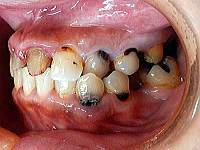

(写真3)ビフォー写真 右側

前歯に装着されていた補綴物が脱離したままで、小臼歯部は欠損が放置されたり冠が外れたままの状態で、

治療が中断されている状態でした。

(写真4)ビフォー写真 左側

天然歯も、カリエスに侵され黒変しており、見た目に虫歯がいっぱいとわかるため、

患者さんも大変気にされていました。